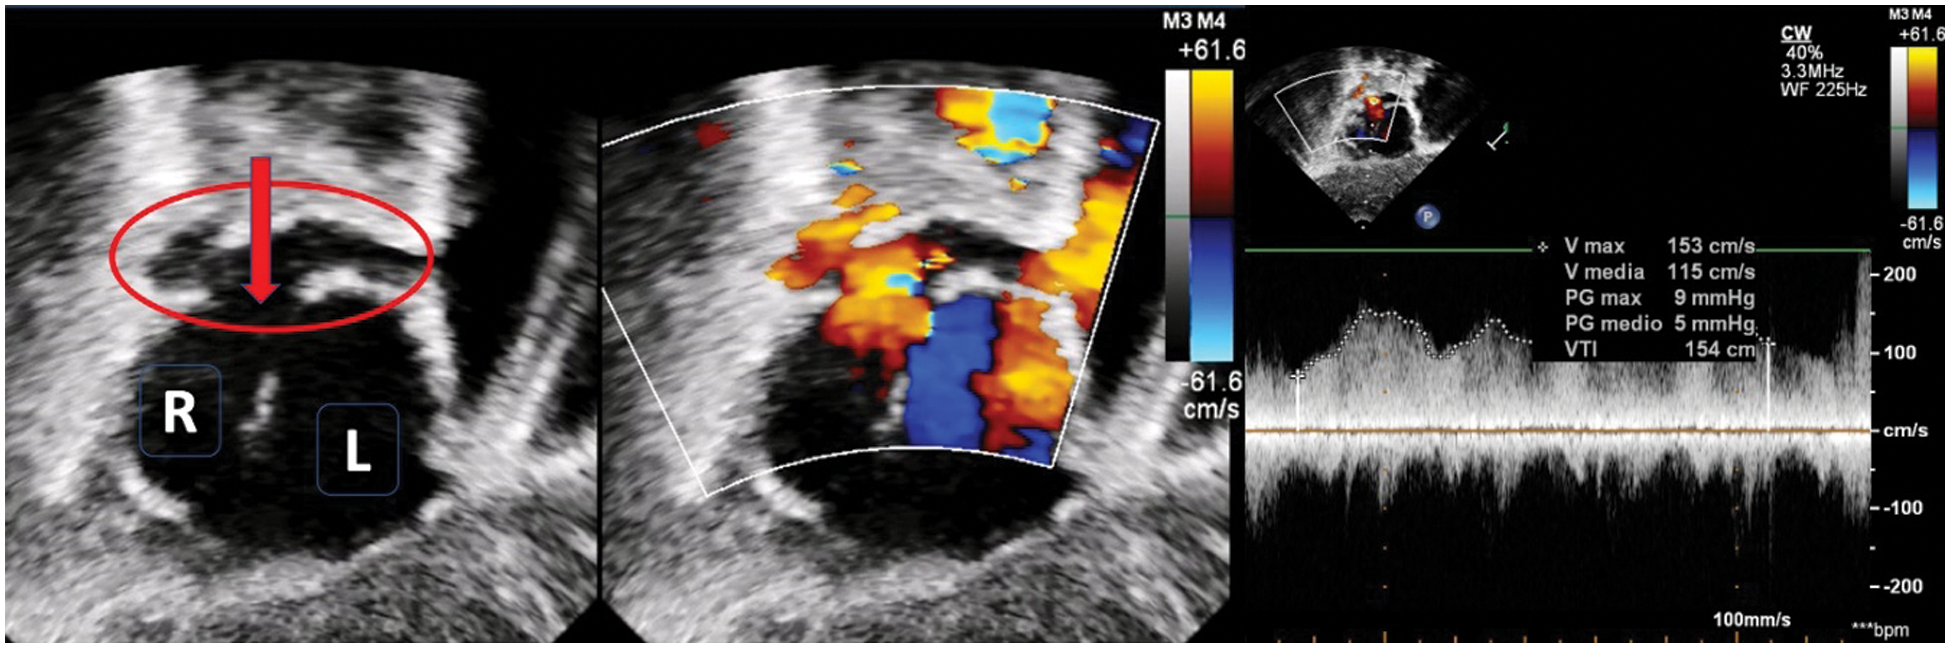

Figure 4: Ultrasound imaging (subcostal view) in a patient with right isomerism and dextrocardia. The left panel shows right-positioned and left-positioned atrial chambers. The red circle shows a retro-atrial confluence of the pulmonary veins which drains into the atrium through an open connection (red arrow). Color-Doppler in the middle and pulsed-wave Doppler in the right panel account for a slightly increased flow velocity through the connection (mean Doppler gradient 5 mmHg)